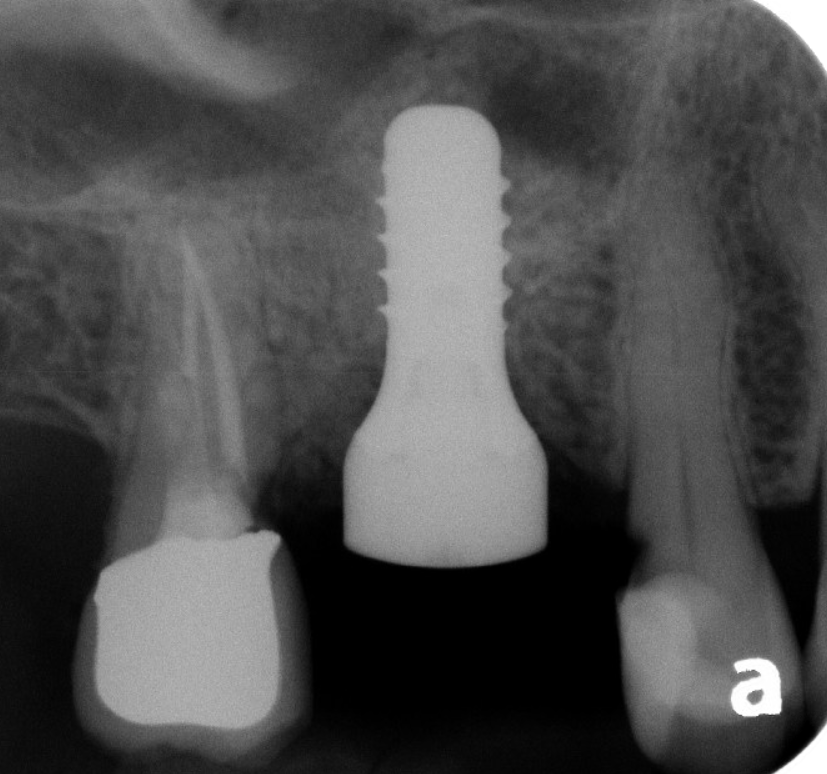

For patients who are missing most or all of their teeth in an arch, the All-on-X protocol (often All-on-4 or All-on-6) is a life-changing solution. Instead of one implant per tooth, we strategically place a specific number of implants (the "X") to support a full bridge of teeth.

A. Hybrid Prosthesis (Fixed)

This is the "gold standard" for permanent tooth replacement.

• How it works: The prosthetic teeth are screwed directly onto the implants.

• Experience: It is non-removable by the patient. It feels the most like natural teeth, offers maximum biting power, and does not cover the roof of the mouth.

Stability: High. It stays in 24/7 and is cleaned just like natural teeth (with specialized flossing tools).